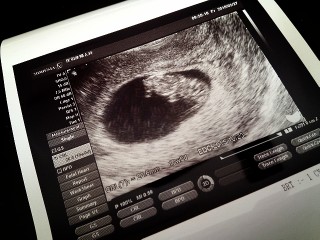

26.6㎜まで順調に育ってました。大きさ的に10w0dみたいです。心臓も赤ちゃん自体もぷよぷよ動いてて可愛かったなぁ。また2週間後が楽しみ。

産婦人科で、順調だし大きさも良いね!と言われました! 前回よりも人間らしくなってて感激!自分の中でこんなすごい進化が起こってるなんてすごく不思議。これからも元気に育ってね☆